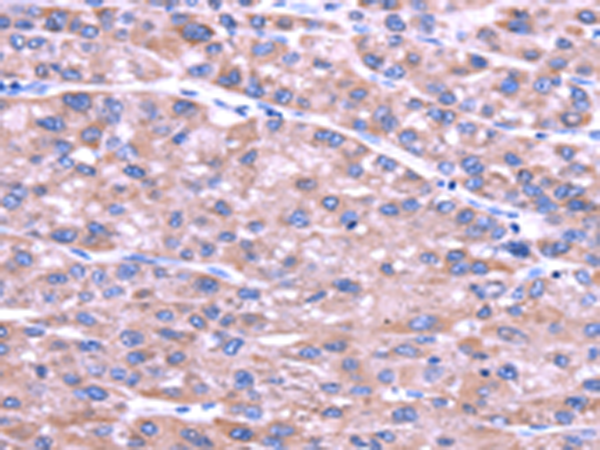

分类: 科研抗体货号: P08755别名: AXAM2; SMT3IP2应用: IHC反应种属: Human, Mouse, Rat